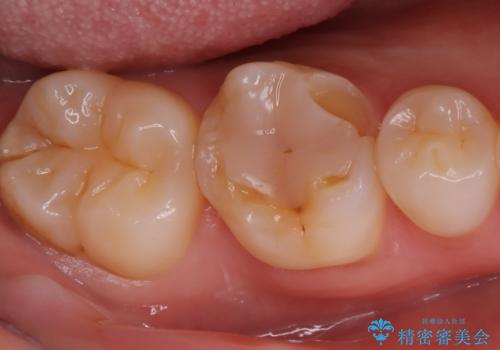

歯が欠けた <セラミッククラウン>

- 主訴は、歯が欠けてしみるとのことでした。欠けた部分が大きいことから、被せものでの治療をおすすめしました。

審美性の良いオールセラミッククラウンを選択されました。